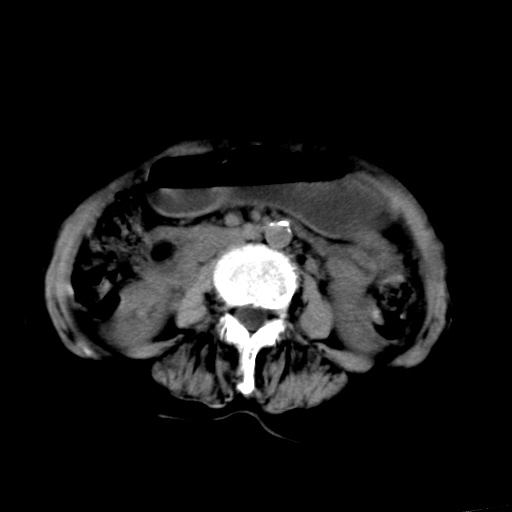

以下是引用杀毒软件在2009-3-4 17:38:00的发言:[br]为何没有喝照影剂呀? 胆总管及肝内胆管扩张,增强吧。[br][br]考虑-----十二指肠占位----建议----十二指肠镜检查[br][br]

以下是引用jiangjing在2009-3-4 17:45:00的发言:[br]低位胆道梗阻。十二指肠降段局部管壁增厚。扫描效果不理想,建议ct增强及ercp。

以下是引用杀毒软件在2009-3-4 17:38:00的发言:[br]为何没有喝照影剂呀? 胆总管及肝内胆管扩张,。增强吧。[br][br]考虑-----十二指肠占位----建议----十二指肠镜检查[br][br][br][br][本贴已被 杀毒软件 于 2009-3-4 17:56:38 修改过]